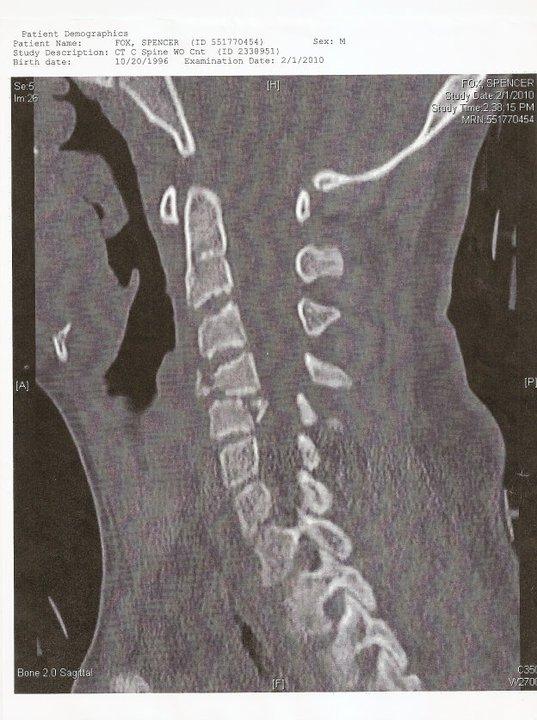

On February 1, 2010, Spencer’s life changed in a split second. He crashed his snowboard and shattered his C4/C5 vertebrae, sustaining a severe and paralyzing spinal cord injury. Unable to breathe, move or feel anything below chest level, Spencer remained hospitalized for over three months. Despite his paralysis and the doctors’ grim prognosis, Spencer never gave up.